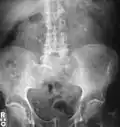

-

Bilateral kidney stones can be seen on this KUB radiograph. There are phleboliths in the pelvis, which can be misinterpreted as bladder stones. -

Calcium-containing stones are relatively radiodense (opaque to X-rays), and they can often be detected by a traditional radiography of the abdomen that includes the kidneys, ureters, and bladder (KUB film).[59] KUB radiography, although useful in monitoring size of stone or passage of stone in stone formers, might not be useful in the acute setting due to low sensitivity.[60] Some 60% of all renal stones are radiopaque.[61][62] In general, calcium phosphate stones have the greatest density, followed by calcium oxalate and magnesium ammonium phosphate stones. Cystine calculi are only faintly radiodense, while uric acid stones are usually entirely radiolucent.[63]